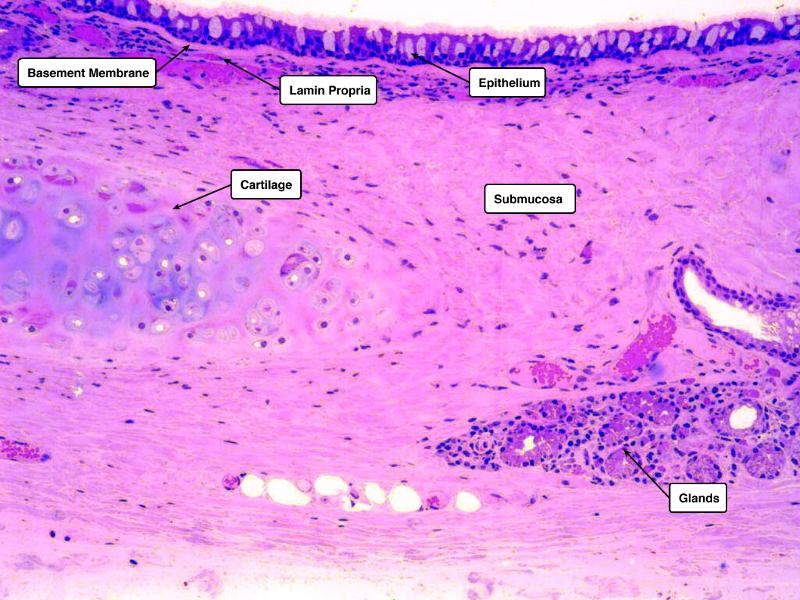

Trace the air flow of respiratory system starting with the nostrils.

What path does a molecule of oxygen take to reach the blood?

What sights will it see along the way?

- Outside air

- ??

- ...

- Toes

Path of O2

- List complete

- With layers

- And cells

- And function of each

- By studying and labelling images

Identify and describe the epithelium on the following slide:

Pseudostratified columnar epithelium

What cells are present?

- Goblet cells

- Basal cells

- Ciliated columnar cells

- Unciliated columnar cells